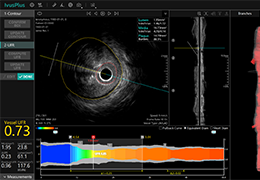

成像智能。

Eclipse 成像智能功能提供强大的处理能力和最佳质量的影像,同时减少质量错误并提高剂量效率。

凭借 AI、专有算法和先进的影像处理能力,提供出色的影像质量和无与伦比的诊断信心。

与标准影像处理相比,智能降噪功能可使客户降低辐射剂量,而不会损失影像质量。这在新生儿和儿科成像中尤其重要,在这种情况下以尽可能低的剂量成像至关重要。